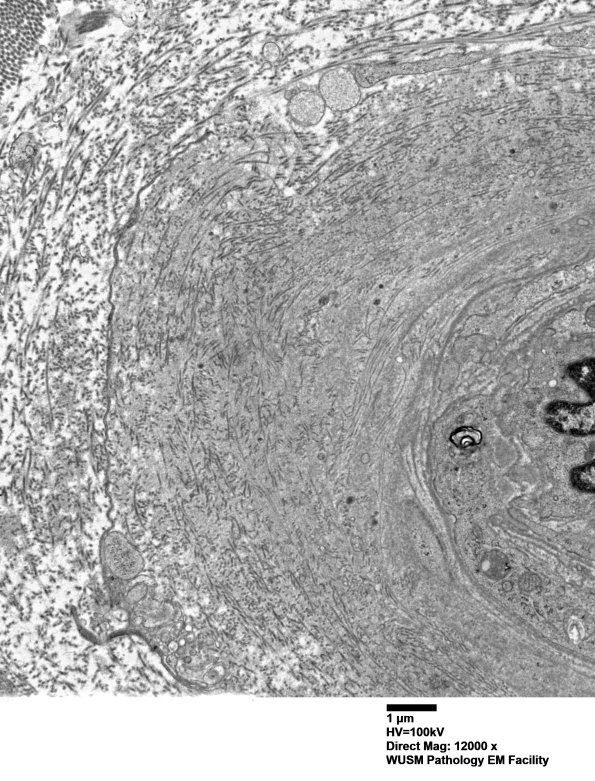

The endoneurial vessel shown here is expanded by collagen deposition with a small contribution by fragments of basal lamina. (electron micrographs)